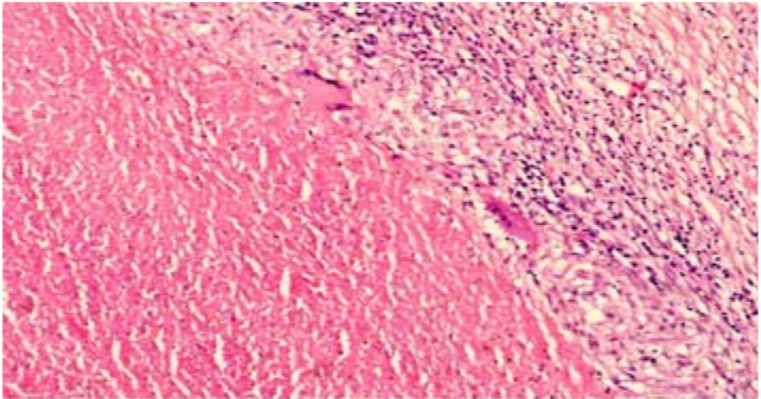

M. tuberculosis in Lymph Node Biopsy Paraffin-Embedded Sections

Our study at Jimma University Specialized Hospital confirmed a high prevalence (61.7%) of tuberculosis lymphadenitis in lymph node biopsies, with a significantly higher occurrence in female patients, necessitating enhanced control and prevention efforts.

Thesis: : M. tuberculosis in Lymph Node Biopsy Paraffin-Embedded Sections.